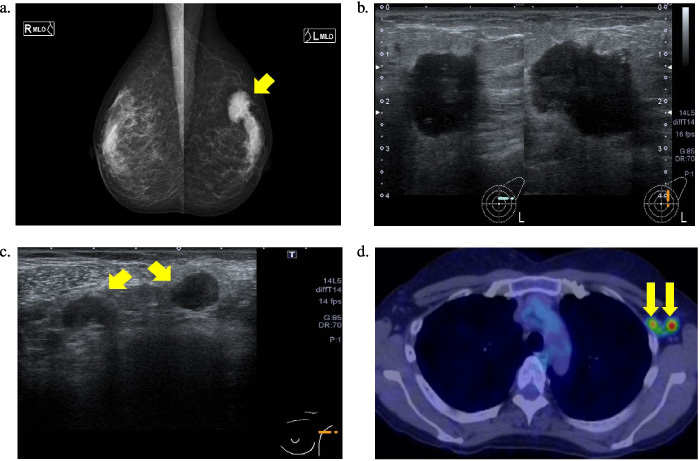

Case presentation: Our patient had a history of BD and was asymptomatic. She was diagnosed with human epidermal growth factor receptor 2-positive breast cancer by core needle biopsy and was administered neoadjuvant chemotherapy. After four courses, in addition to the aggravation of the existing adverse events, headache, fever, dysarthria, and muscle weakness in the upper left and lower extremities appeared. On admission, she was diagnosed with acute NBD, and steroid therapy was initiated. After her symptoms improved gradually, she was discharged. Then, she underwent mastectomy and axillary lymph node dissection for breast cancer. Trastuzumab and pertuzumab plus tamoxifen were administered postoperatively. Two years postoperatively, no recurrence of breast cancer and NBD was noted.